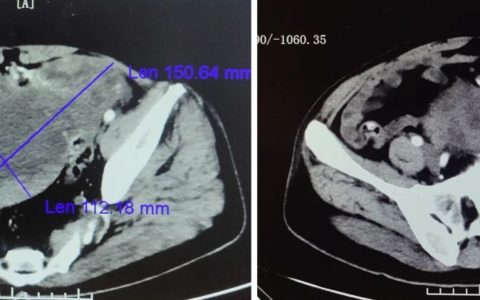

下午3:15分,做完检查的马先生被送至手术室,麻醉医师及护理团队立即为马先生进行输血抗休克等“保命”治疗。在手术室等候多时的手足显微外胡朝波主任与周塏医生小心翼翼的打开伤口敷料,不由得眉头紧锁:只见马先生的右手臂从肩关节下方约8厘米处完全离断,仅手臂后侧约2厘米宽皮肤相连,近端肩关节的皮肤也呈脱套状多处撕裂,创面内可见断端肌肉被绞成肉泥状,主要神经血管均呈马尾状抽出离断,其中正中神经和尺神经从前臂中段抽出长达25厘米。更严重的是,马先生的右肘关节脱位,前臂也受到严重绞伤,尺桡骨中段均粉碎性骨折,再植难度非常大,极具挑战性!而如果只是简单粗暴地截去一条手臂,患者的工作和日常生活质量必将受到严重影响。

面对患者及家属强烈的保肢意愿,胡朝波主任仔细评估伤情后,迅速制定了手术计划。麻醉成功后,他带领着手足显微外科医生团队迅速上台,先“地毯式”清创去除坏死和污染组织,评估神经血管缺损长度,截短相应长度的肱骨以确保神经血管能直接缝合,然后在显微镜下一丝不苟地缝合了多条血管,下午六点,在马先生伤后的第5个小时、被送入手术室后的一个半小时后,马先生的断肢血管重新被接通,看着他右手各个手指逐渐转红润,手足显微外科医生团队不由得松了一口气,终于抢在断肢再植“6-8小时的黄金时间段”内完成了肢体的血管再通,这样就意味着断肢再植手术后并发症更少,愈后组织功能恢复也会更好。接着,手术团队按计划有条不紊地对断肢进行创面止血、骨折固定、神经修复、肌肉缝合、筋膜切开减压及创面覆盖引流……经过持续6个多小时的持续操作,晚上10点多,手术终于结束,马先生被送入ICU进一步治疗。